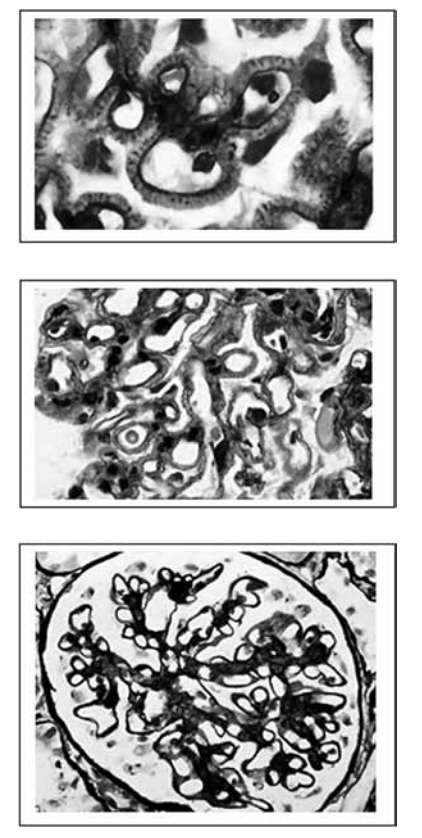

Adolescente de 12 anos, sexo feminino, apresenta quadro de edema de face, redução da diurese e espuma na

urina. No exame físico, apresenta edema generalizado

com pressão arterial normal.

Exames laboratoriais:

Ureia: 23 mg/dL Creatinina: 0,9 mg/dL Albumina sérica: 2,8 g/dL Colesterol total: 260 mg/dL Triglicérides: 240 mg/dL C3: 158 mg/dL C4: 21 mg/dL

Urina I: pH: 7,0 Densidade: 1.015 Proteínas: presentes Hemácias: 3.000 Leucócitos: 2.000

Proteinúria 24h: 3g/24h FAN: negativo Sorologia para vírus B, C e HIV: negativa VDRL: reagente 1/128 Sorologia para Treponema pallidum: > 3,0

Resultado da biopsia apresentado a seguir:

(Agnes B. Fogo, Fundamentals of Renal Pathology)

Considerando os dados e as imagens apresentados, assinale a alternativa que indica o provável diagnóstico.